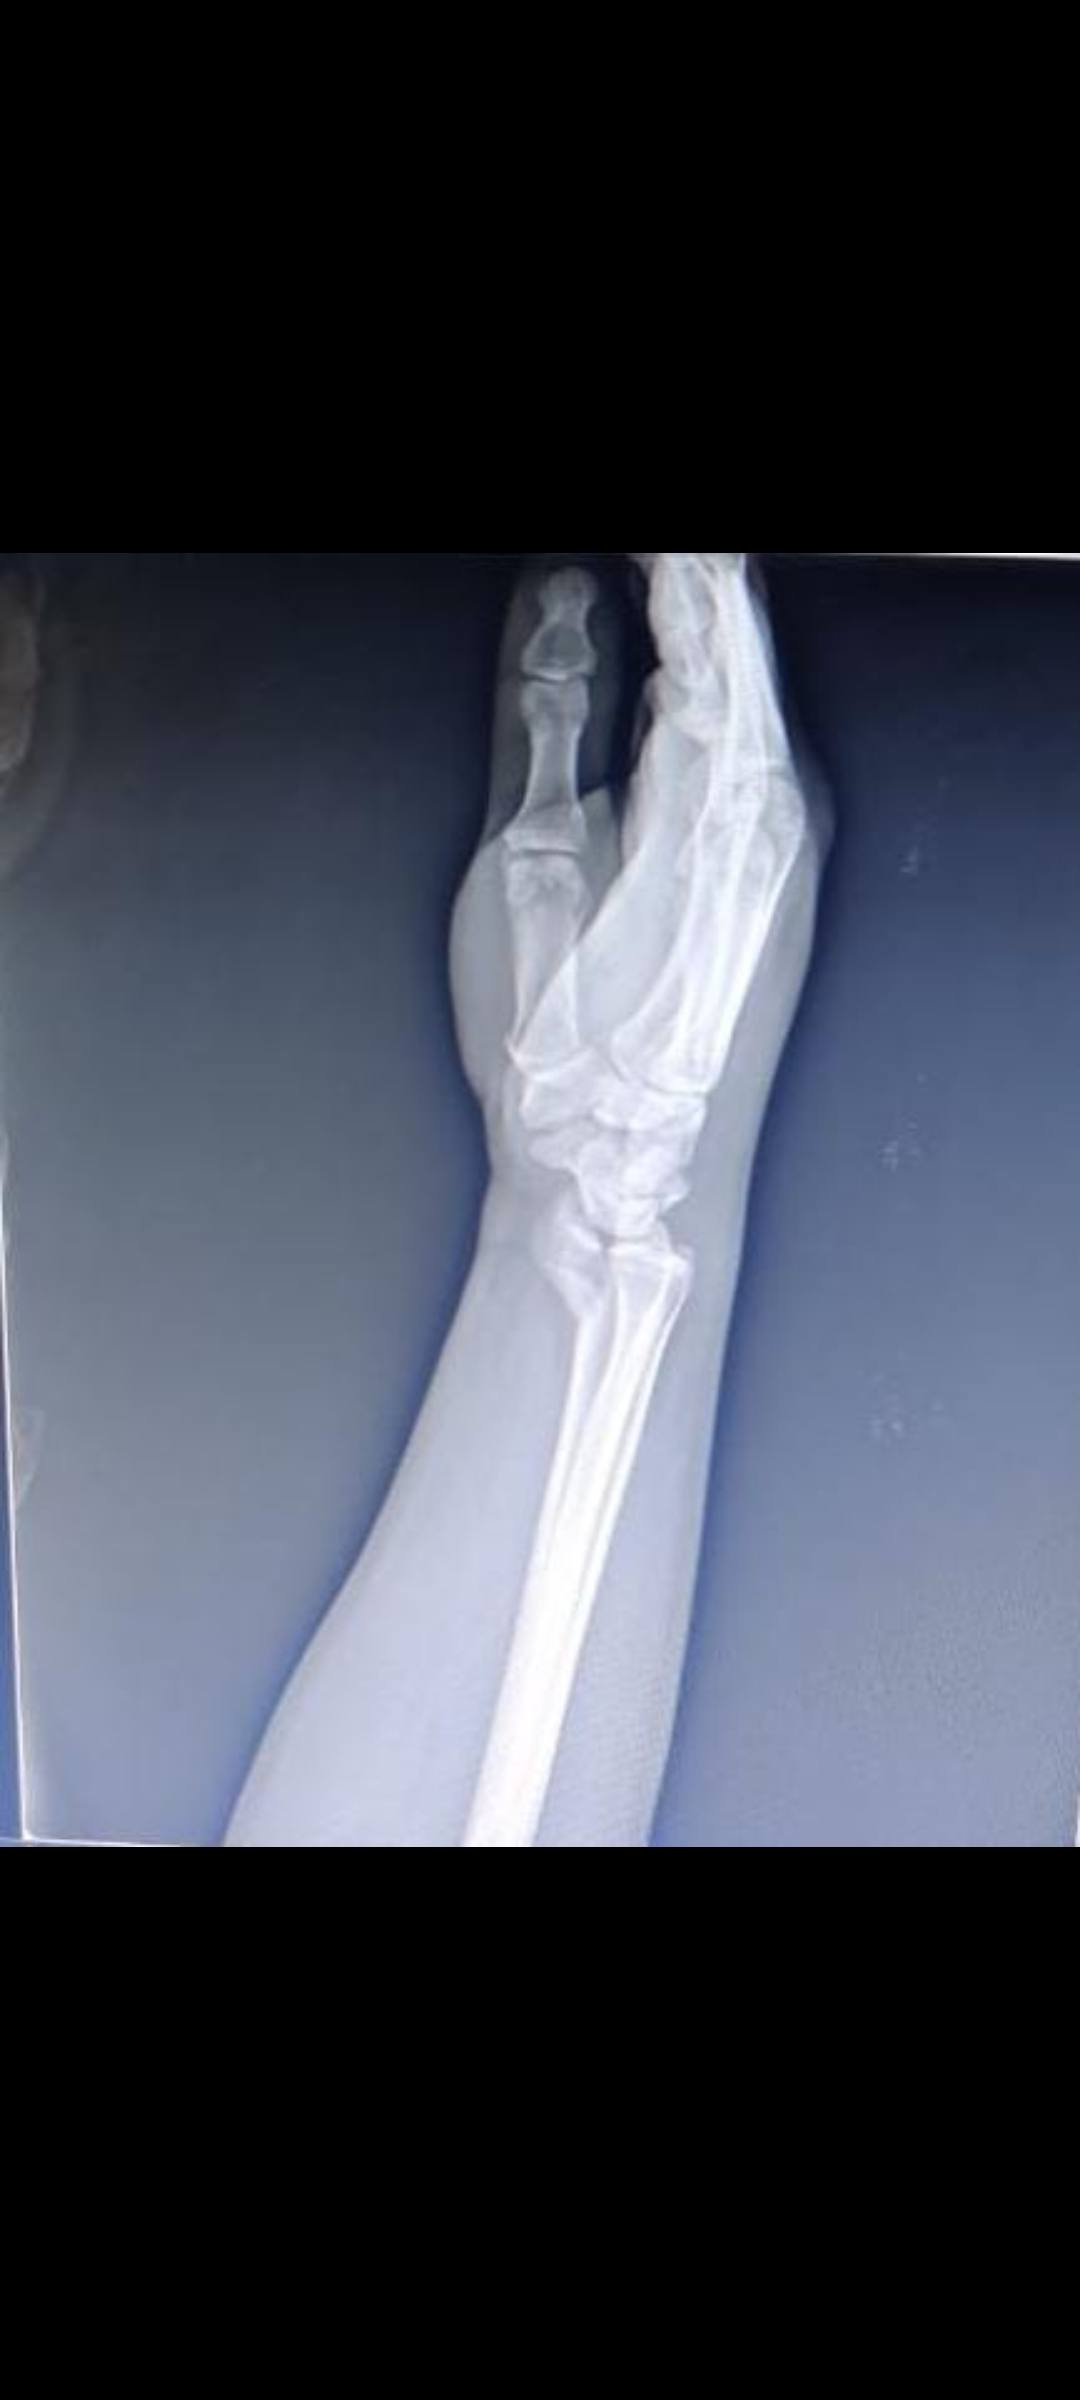

Sandip Jadhav